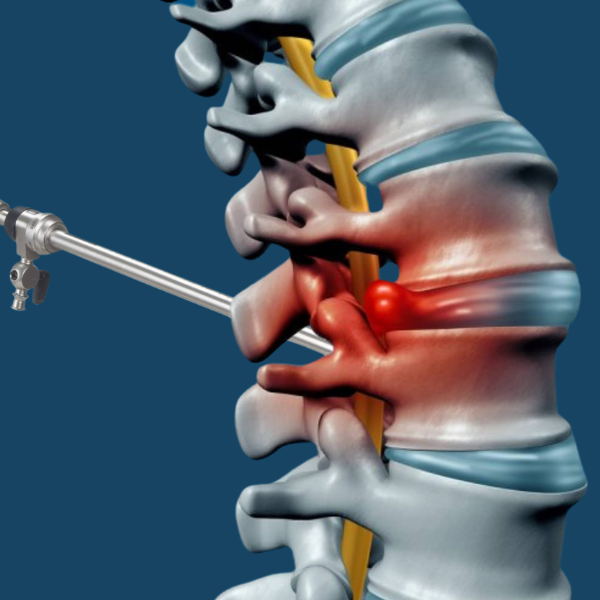

Minimally Invasive Spine Surgery

Minimally invasive spine surgery uses small incisions and advanced techniques to treat conditions like herniated discs, spinal stenosis, and degenerative disc disease. This approach reduces recovery time and minimizes risk, allowing patients to return to their daily activities faster.